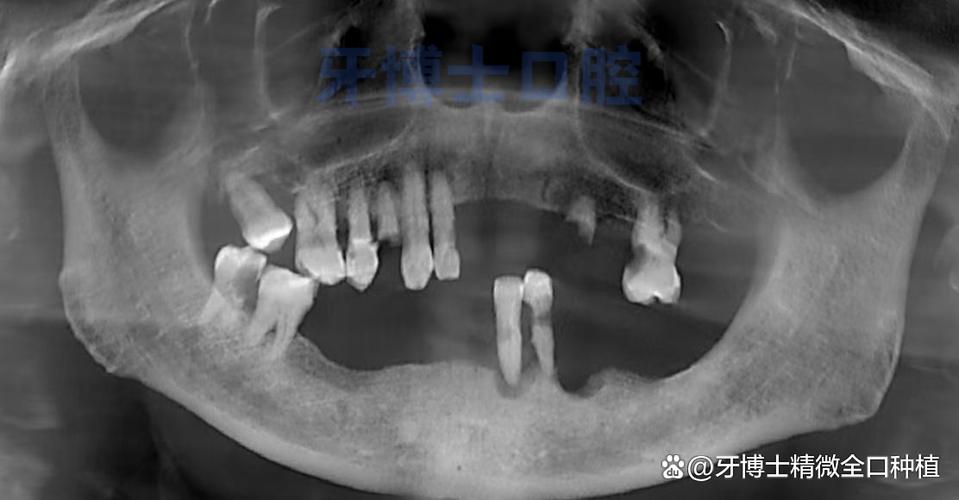

牙周炎是导致上牙松动的首要原因,其核心是牙菌斑积累引发的慢性炎症,长期未清洁的牙菌斑会形成牙结石,刺激牙龈组织,导致牙龈炎;若未及时干预,炎症会向深层发展,破坏牙周膜和牙槽骨,牙槽骨如同房屋的地基,一旦吸收,牙齿失去支撑便会逐渐松动,尤其上颌前牙(门牙)位于口腔前部,受力频繁,牙槽骨吸收后松动更为明显,侵袭性牙周炎可能短时间内造成广泛牙槽骨破坏,导致牙齿快速松动,甚至脱落。

咬合创伤分为急性创伤和慢性创伤,急性创伤如外力撞击、咬硬物(如开啤酒瓶、啃骨头)等,可能导致牙根或牙周组织瞬间受损,出现牙齿松动、疼痛;慢性创伤则多由咬合异常引起,如夜磨牙、紧咬牙(导致非功能性咬合力)、牙齿过高咬合干扰、缺牙后邻牙倾斜受力不均等,长期异常咬合力会使牙周膜持续处于微创伤状态,引发牙槽骨改建(吸收),最终导致牙齿松动,上颌磨牙因对颌牙缺失而过度伸长,形成“早接触”,长期受压后可能出现松动。

当牙齿因龋齿、外伤等原因导致牙髓坏死,感染通过根尖孔扩散至根尖周组织,引发根尖周炎时,根尖周围可能出现骨质破坏、脓液积聚,炎症会刺激牙槽骨吸收,导致牙齿浮起、松动,同时伴有咀嚼疼痛、根尖部牙龈肿胀等症状,若根尖周病变长期未治疗,可能破坏牙齿的支持组织,即使未累及牙周袋,也会出现松动。